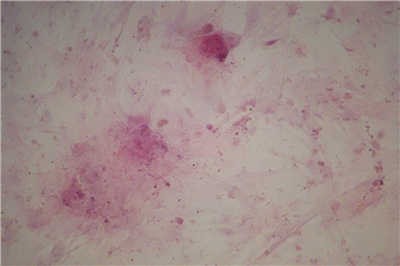

1.成骨诱导的过程是使钙离子能够以钙盐的方式沉淀下来,即“钙结节”,鉴定钙结节的染色方法常用茜素红染色法。

3.染色原理:茜素红与钙发生显色反应,产生一种深红色的带色化合物,这样成骨诱导的细胞外面沉积的钙结节也就被染成了深红色。.